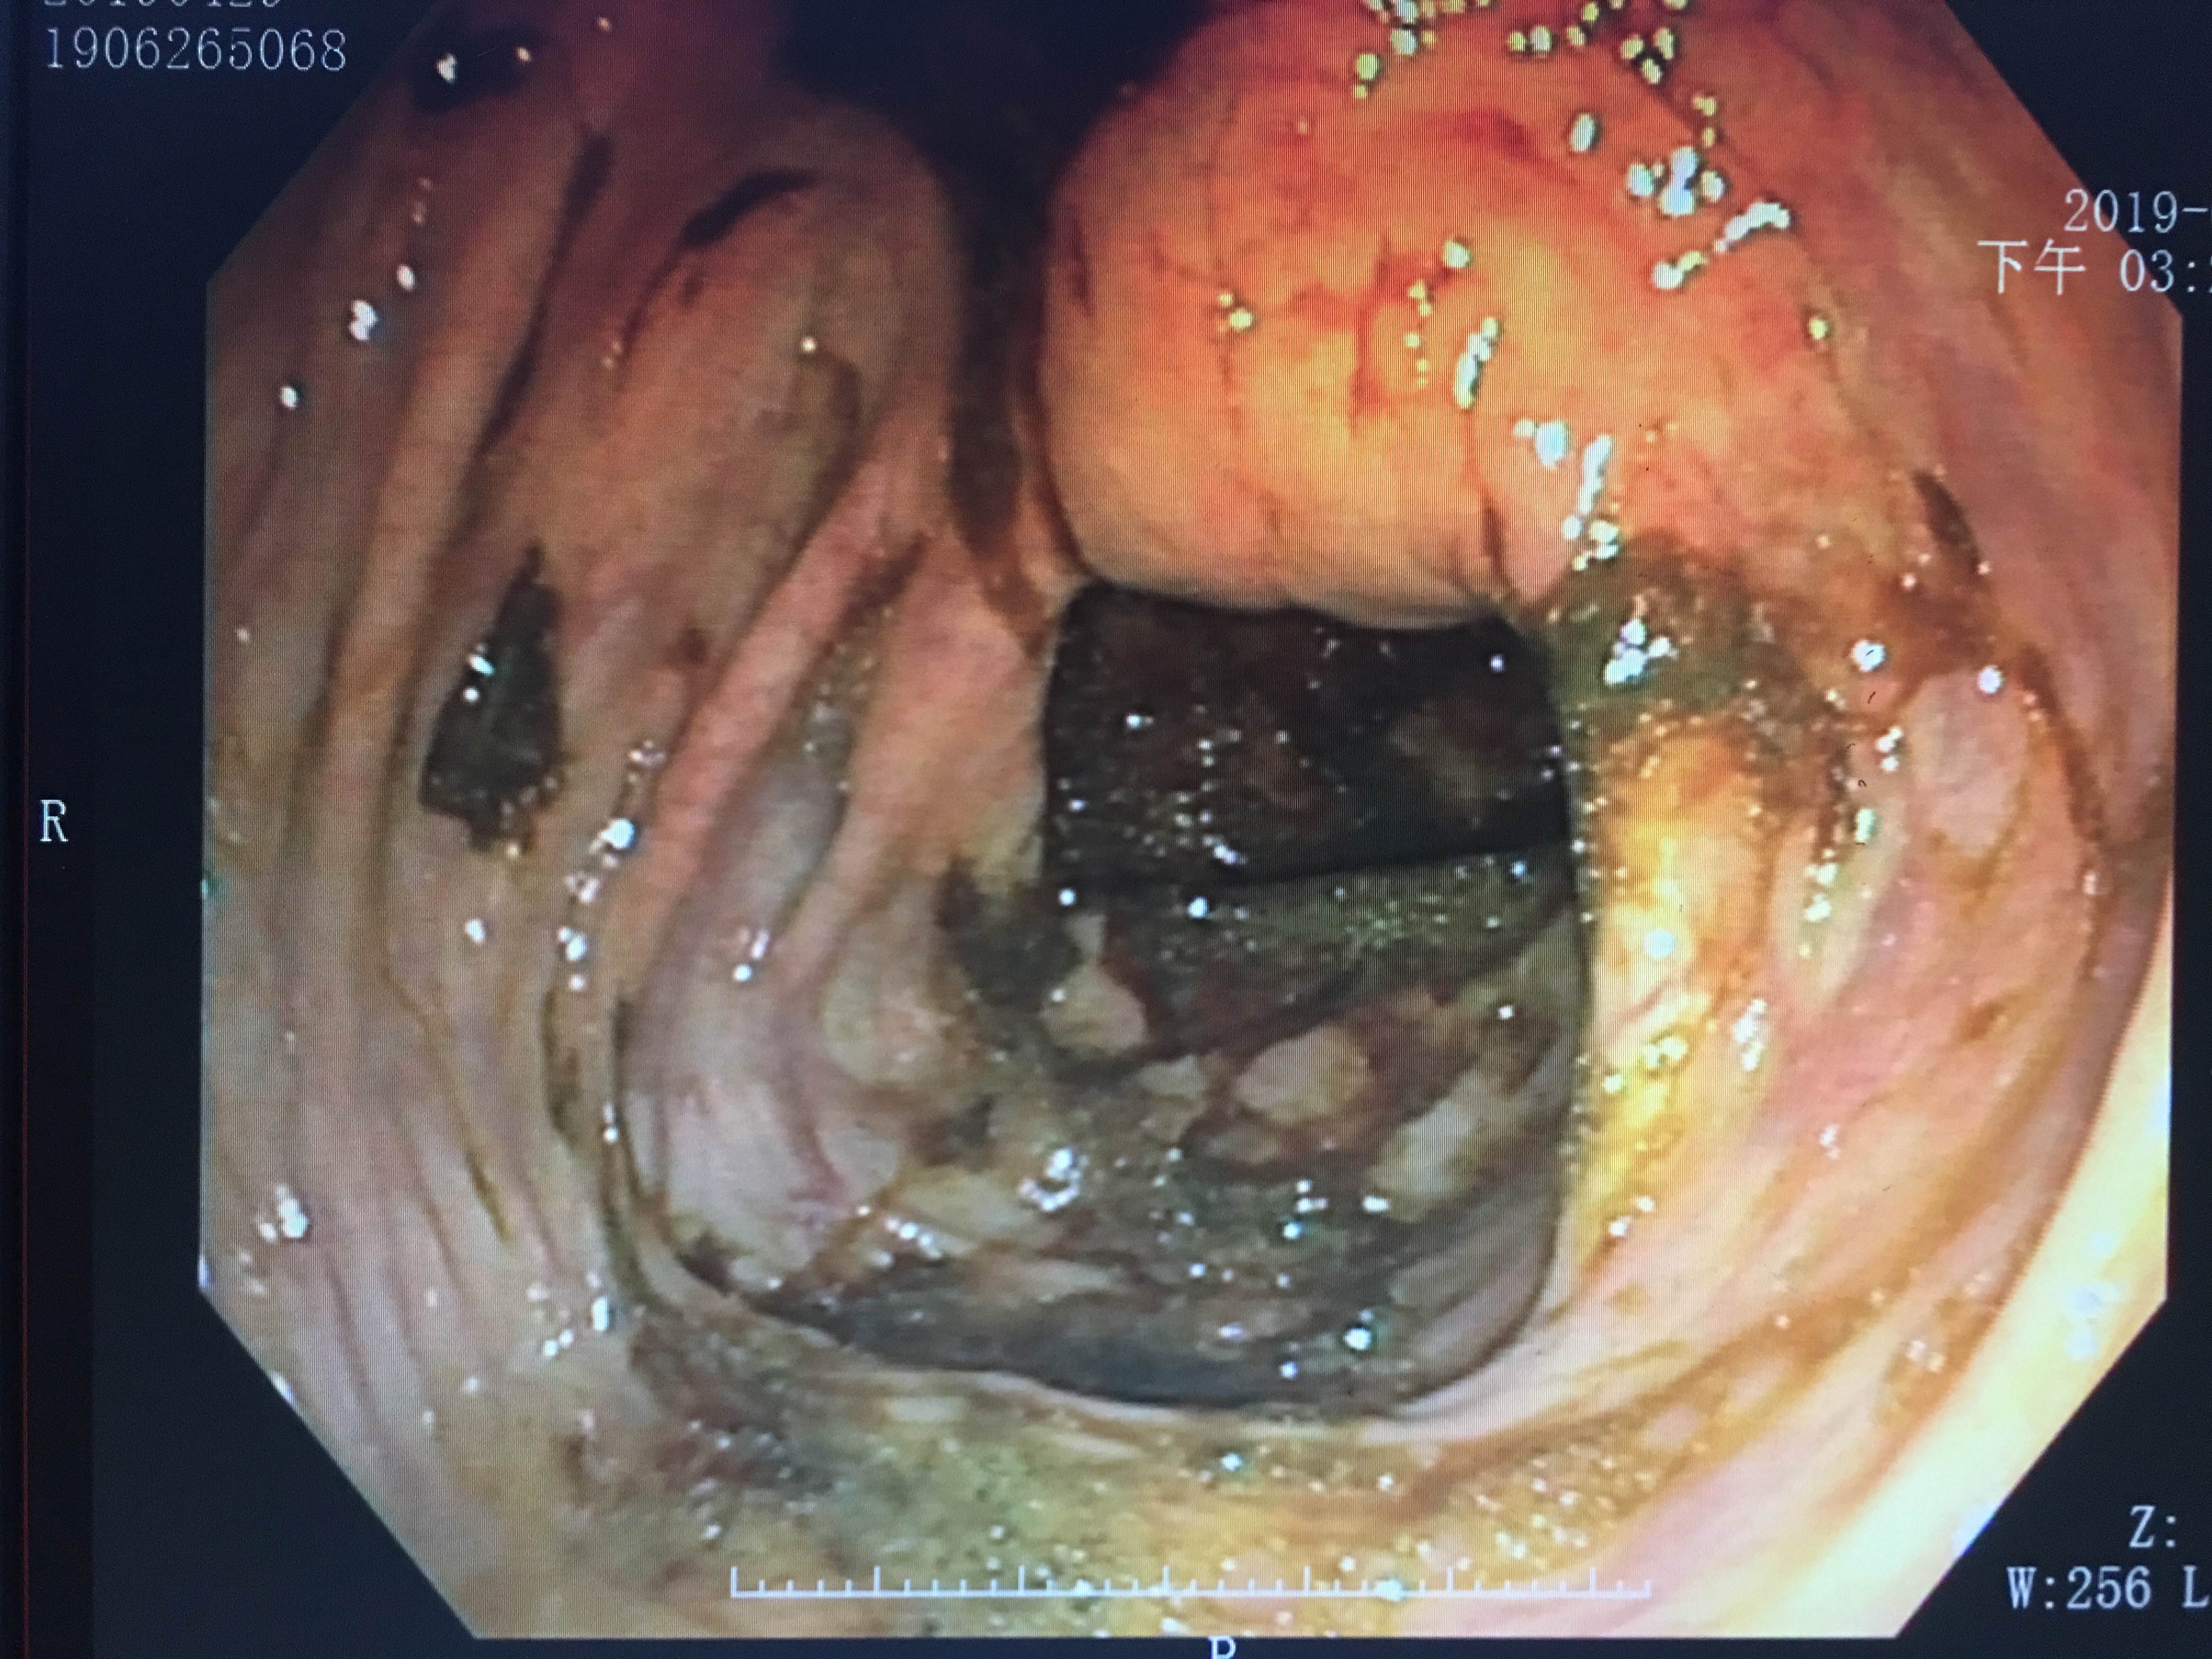

偷吃巧克力病人的胃镜视野

如果不是十分熟练经验丰富的医生,看到这样的景象,第一反应就是“上消化道出血?”。然而,图中却是一个偷吃巧克力患者的图像。请问,这样的景象,你想要的医生看出什么端倪?

吃进去的食物,经过口腔咀嚼以及胃部蠕动消化,会覆盖在胃粘膜的表面,当胃镜伸进去的时候,看到的就是“狼藉”战场。所以,胃镜之前严格禁食是很重要的。